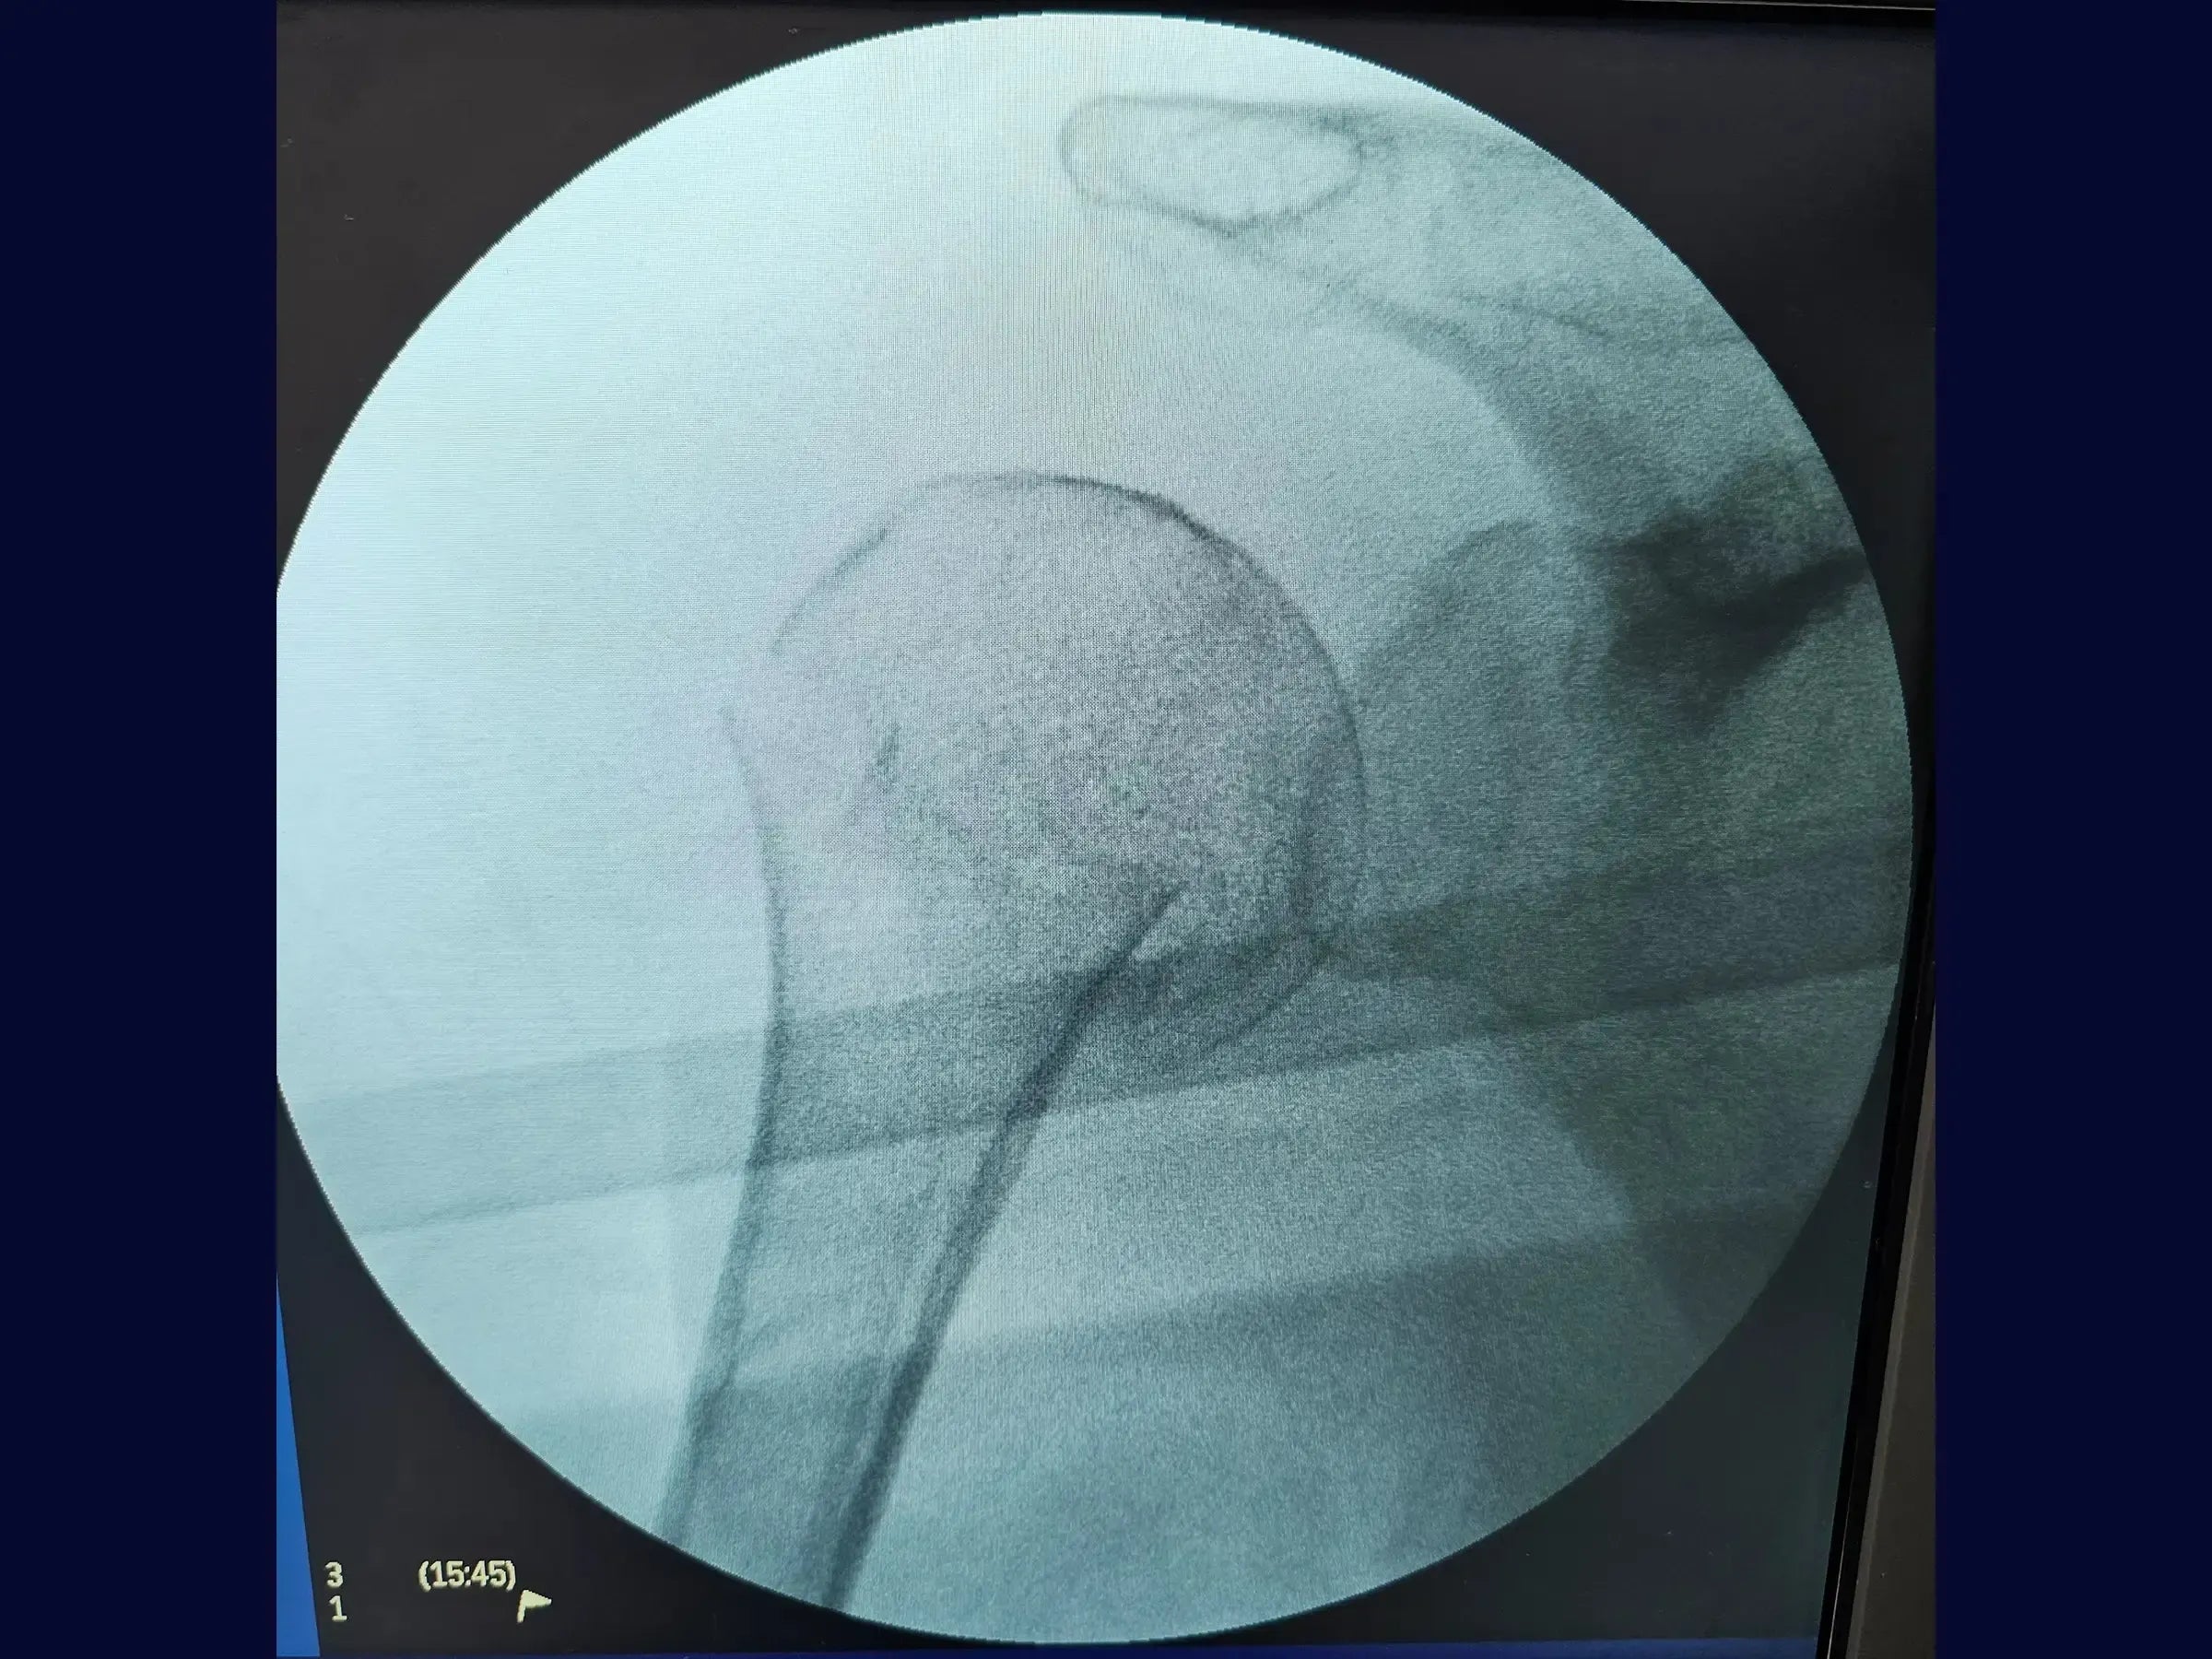

A complexidade das fraturas do úmero proximal exige abordagens que preservem a função e minimizem a morbidade. Este treinamento oferece uma imersão técnica na osteossíntese com haste intramedular, utilizando acessos minimamente invasivos e uma técnica de manipulação do fragmento proximal com "joystick", focando na recuperação do eixo, rotação e versão da cabeça umeral sem a necessidade de uma redução anatômica precisa.

- Osteossíntese de fraturas do úmero proximal com haste intramedular.

- Otimização da Introdução do Fio Guia: Estratégias para posicionamento preciso do fio guia na cabeça umeral, auxiliado por conferência radiográfica e pelo uso do "joystick" para obter imagens AP e lateral.